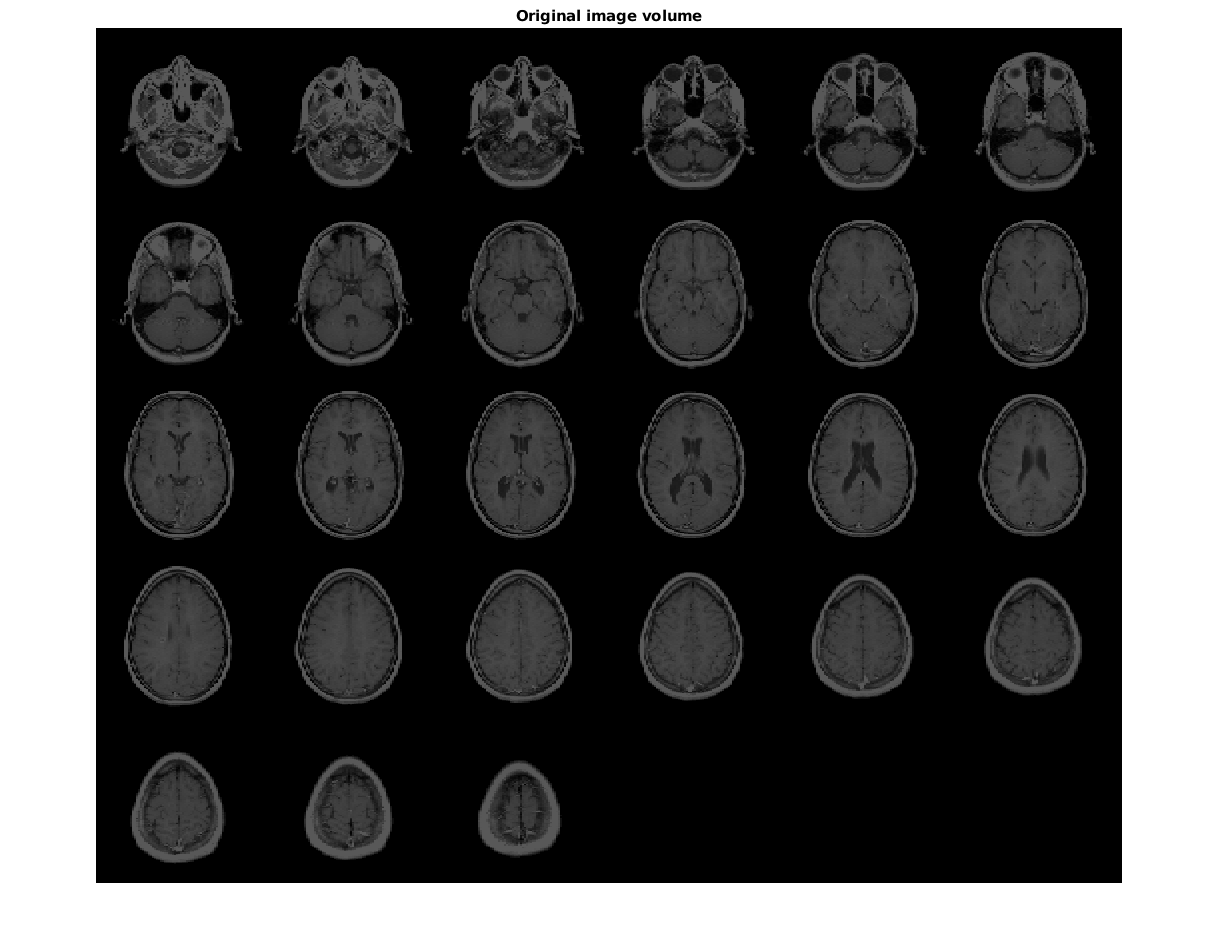

Загрузите данные МРТ и отобразите их.

vol = load('mri');

figure

montage(vol.D)

title('Original image volume')

Figure contains an axes. The axes with title Original image volume contains an object of type image.